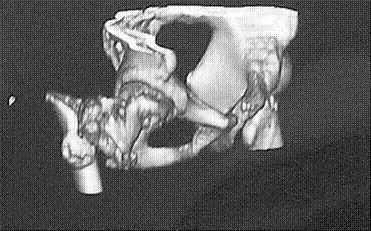

Уважаемые коллеги! Нужен совет. Больной Х., 21 год, ДЗ: ложный сустав вертельной области

правого бедра. Травма 8 мес. назад, ДТП, получил закрытый межвертельный перелом правого

бедра. Лечился в городской больнице одного из городов-спутников г. Караганды скелетным

вытяжением в течение 3 недель, затем кокситной гипсовой повязкой 2 мес.

В настоящее время имеется укорочение конечности на 7 см, умеренная

боль в вертельной области; ходит без костылей, полностью нагружая

больную конечность, при нагрузке отмечается смещение дистального

отломка проксимально примерно на 1,0 см.; объем движений в коленном

суставе сохранен; при пальпации отломков боли нет, умеренная

патологическая подвижность.